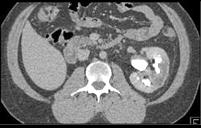

男,47岁,左侧腰痛、叩击痛,请结合图像,选择最可能诊断 ( )A、左肾脓肿B、左肾挫伤C、左肾癌D、左肾梗死E、左侧肾盂肾炎

问题 男,47岁,左侧腰痛、叩击痛,请结合图像,选择最可能诊断 ( )

选项 A、左肾脓肿 B、左肾挫伤 C、左肾癌 D、左肾梗死 E、左侧肾盂肾炎

答案 D